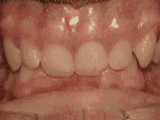

Openbite: Front teeth don't touch

Patient sucked her thumb as a young child. She started treatment at age thirteen. She had braces and a special appliance — called a crib — to retrain the tongue, for twenty-eight months. Now she can bite the lettuce out of a sandwich.